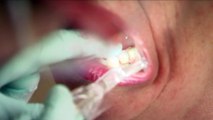

As cost-of-living pressures rise, one thing dropping off the priority list for some, is visiting the dentist. An increasing number of older Australians are ending up in hospital for preventable dental treatment. The Australian dental association says the answer is for the government to fund a senior’s dental benefits scheme.